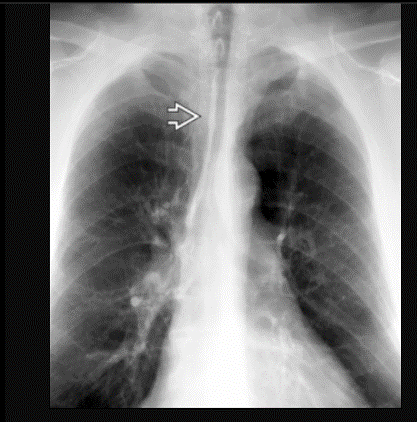

Saber sheath trachea, pathognomonic for COPD

Best diagnostic clue: Side-to-side narrowing of intrathoracic trachea